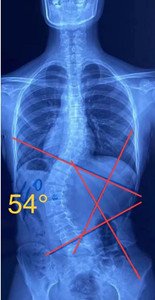

单向侧弯

如果是单向侧弯的患者,(腰弯或者胸弯),躺在床上,应向患侧处进行卧位,侧卧在你弯弧的凹侧,让它下坠打开。

s型侧弯,无论向哪个方向侧躺,对其中一边的弯度都是不利的,这种情况尽量以平躺为主。